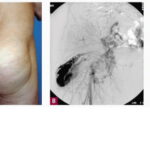

Arteriovenous malformation =تشوه شريني وريدي